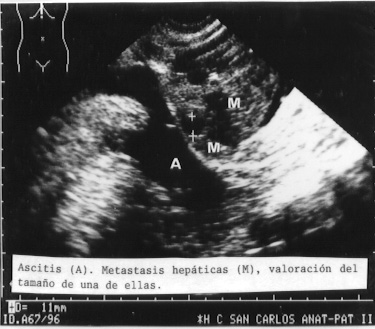

La patología en el hígado fue fácil de demostrar. Como ejemplos presentamos las figuras 15, 16 y 17 de cirrosis, cirrosis con hepatocarcinoma y de metástasis tumoral.

17METASH.JPG (44335 bytes)

Fig 17